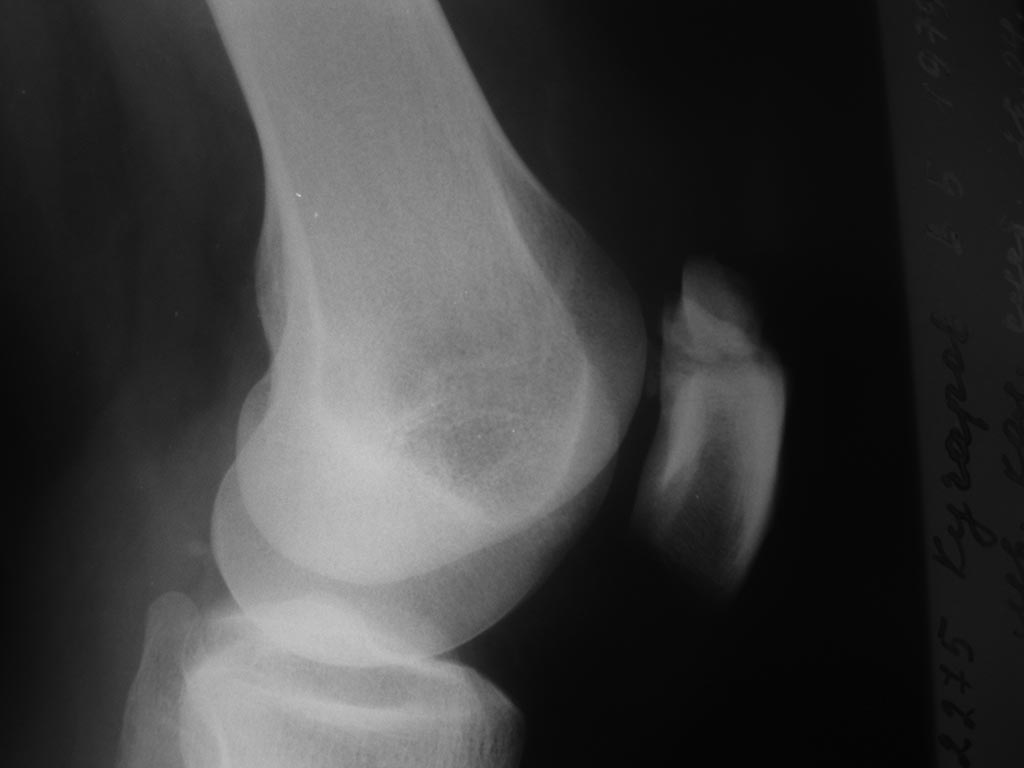

[Ortho] ложный сустав надколенника

Уважаемые коллеги! поделитесь мыслями об вариантах оперативного лечения

ложного сустава

надколенника. С момента травмы прошло больше года.